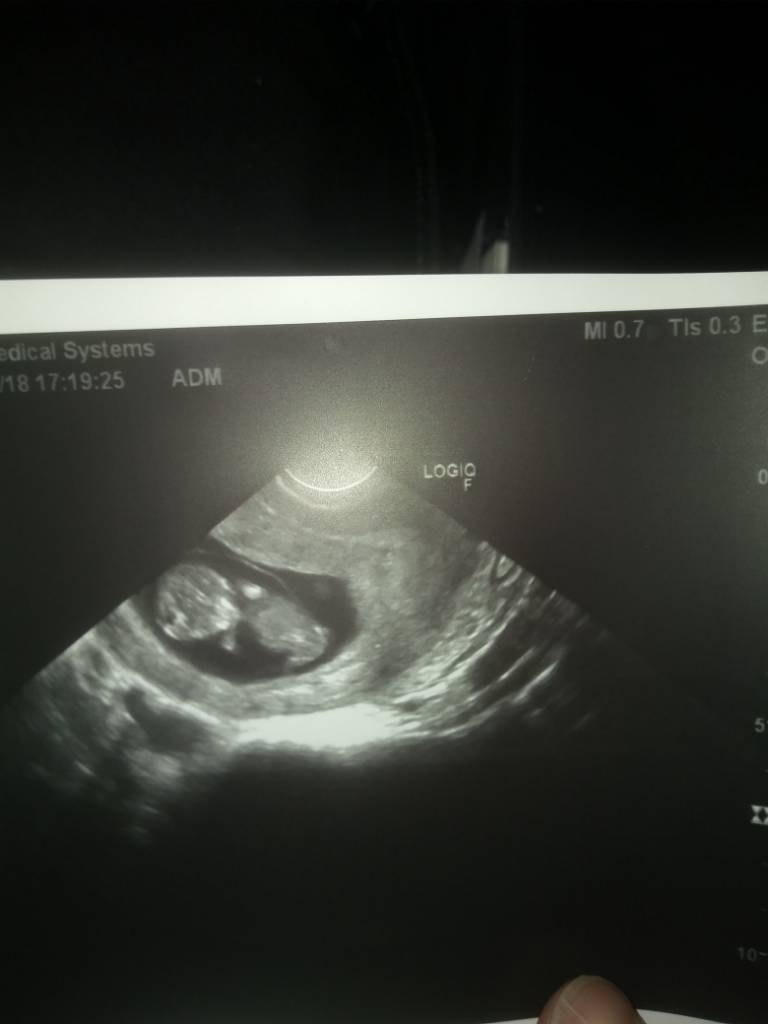

Super dzidziolek! Z teorii Ramziego dziewczyny już by wróżyły chłopca [emoji39] w co oczywiście nie wierzę jakoś specjalnie i trochę tygodni minie zanim się dowiesz. [emoji4]

To u mnie też chyba chłopiec?

20181115_175254.jpg

• 20181115_175254.jpg

29,9 KB · Wyświetleń: 348